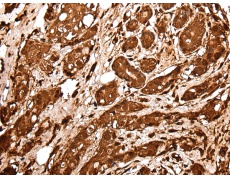

IHC positive control: |

Human prostate cancer and human tonsil |

IHC Recommend dilution: |

25-100 |